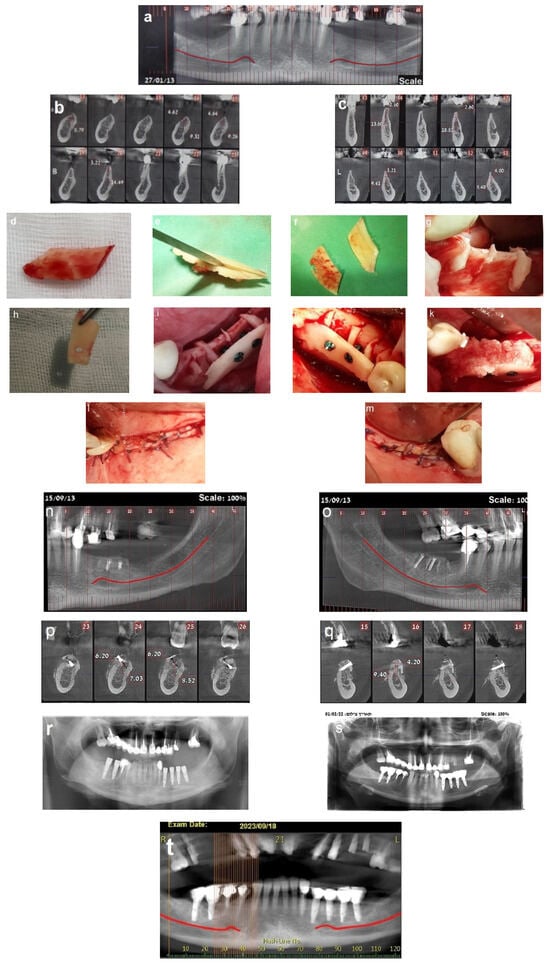

A 36-year-old woman was referred for bone augmentation and dental implant placement in the atrophic posterior mandibular ridges. The examination revealed partial edentulism of the mandible, with missing posterior teeth on both the right and left sides (Figure 6a). Computed tomography confirmed a significant horizontal bone deficit in the posterior mandibular regions bilaterally (Figure 6b,c). A two-stage treatment approach was planned. In the first stage, the honeycomb bone (HCT) technique was employed to augment the right and left posterior mandibular regions.

Figure 6.

(a) Bilateral posterior mandibular edentulism. (b,c) Computed tomography showing severe horizontal atrophy with knife-edge residual ridges. (d) The bone block harvested from the retromolar donor site. (e,f) The harvested bone block and its subsequent splitting, resulting in thin bone blocks and cortical wedges. (g) The bone augmentation procedure: grooves were created using high-speed at the recipient site, followed by the insertion and tapping of the cortical bone wedges into the grooves. (h,i) A thin bone plate is positioned over the bone wedges and secured with screws, creating bone compartments resembling a honeycomb. (j) Right side. (k) The bone compartments are filled with allogenic particulate bone graft to achieve the desired graft volume on the right side. (l,m) Double-layer, tension-free closure of the recipient sites performed using BFFGs. (n–q) CBCT scan, four months postoperatively show significant bilateral horizontal bone gain. (r) Two implants were placed on the right side and four implants on the left side. (s) Panoramic view at 8-year follow-up. (t–v) CBCT scans taken 10 years after implant placement reveal stable augmented bone levels. (w) Eleven-year follow-up periapical x-ray of the left side, demonstrating no significant marginal bone loss. (x) 3 mm of marginal bone loss observed at the mesial implant. The yellow arrows show the cortical wedges that remain visible at the recipient sites.

In May 2013, a cortical bone block was harvested from the right retromolar area (Figure 6d). The harvested block was then split, yielding two thin bone blocks and multiple bone wedges (Figure 6e,f). The recipient sites were prepared by creating grooves, into which the bone wedges were inserted in a stable position bilaterally (Figure 6g). Two thin bone blocks were then secured over the bone wedges using screws. This configuration resulted in multiple bone compartments resembling a honeycomb structure (Figure 6h–j). After trimming any sharp edges, the compartments were filled with particulate allograft bone substitute, achieving the desired final bone volume (Figure 6k). The augmented sites were then covered with a resorbable membrane and a free buccal fat pad graft (BFFG) before being closed in a tension-free manner (Figure 6l,m). The healing process was uneventful throughout the follow-up period. A CBCT scan performed four months postoperatively, in September 2013, confirmed significant horizontal bone gain of 4–6 mm (Figure 6n–q). Upon reentry under local anesthesia, the newly formed bone volume was evident, with the bone wedges fully integrated into the regenerated bone mass. Six dental implants were successfully placed (Figure 6r). After three months, all the implants had achieved full osseointegration, allowing for final prosthetic rehabilitation. This case has been followed for 11 years. A panorex obtained at 8 years showed implants without marginal bone loss (Figure 6s), and a CBCT scan obtained in September 2023 demonstrated stable bone volume 10 years post-surgery, with no resorption of the augmented bone blocks (Figure 6t–v). Periapical radiographs taken in July 2024 further confirmed the long-term stability of the outcomes and implant survival. At this time, the first implant on the right side showed a 3mm marginal bone loss, possibly due to food impaction from a decayed adjacent premolar. The remaining five implants exhibited no signs of marginal bone loss. The cortical wedges remained visible at the recipient sites in both figures (Figure 6w,x).